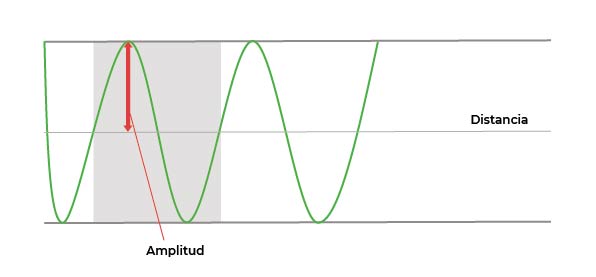

Amplitud

Volvamos un segundo a la onda mecánica del sonido. La amplitud del sonido es una medida de la variación máxima de desplazamiento de esa onda, y su unidad son los decibelios (dB). La amplitud está relacionada con la intensidad del sonido, y es clave en la interacción con el cuerpo del paciente.